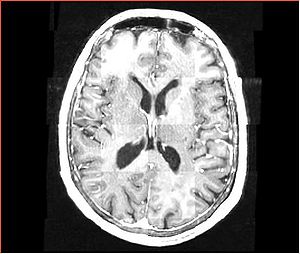

• Input images: isotropic post-contrast T1 MRI acquired at different locations of BWH during 2006-2008, used under medical records study IRB. Time period between acquisition of scans for each patient is about 1 year.

• images were acquired with the same sequence, but possible on different scanners, all scans are axial